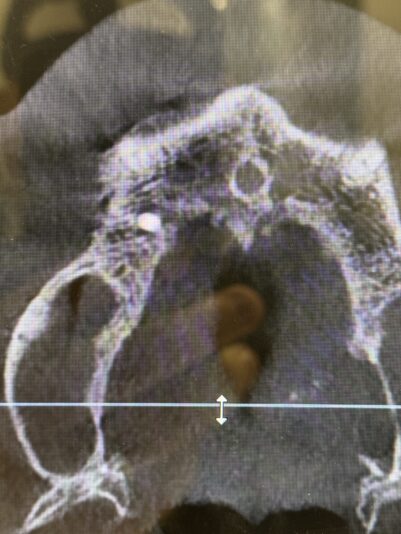

• Looks good, right?!? Not once you see the cbct and create a larger full thickness flap. What would you do here? What are your options? This happened during one of our live surgery courses. Please leave a comment below on what you would do and a couple options we may have. After I recieve several comments I will post a follow up post next week…

Read more

• implant position looks too buccal to me in this photo. i’d remove and start a new osteotomy and sink the implant to the level of the lingual bone